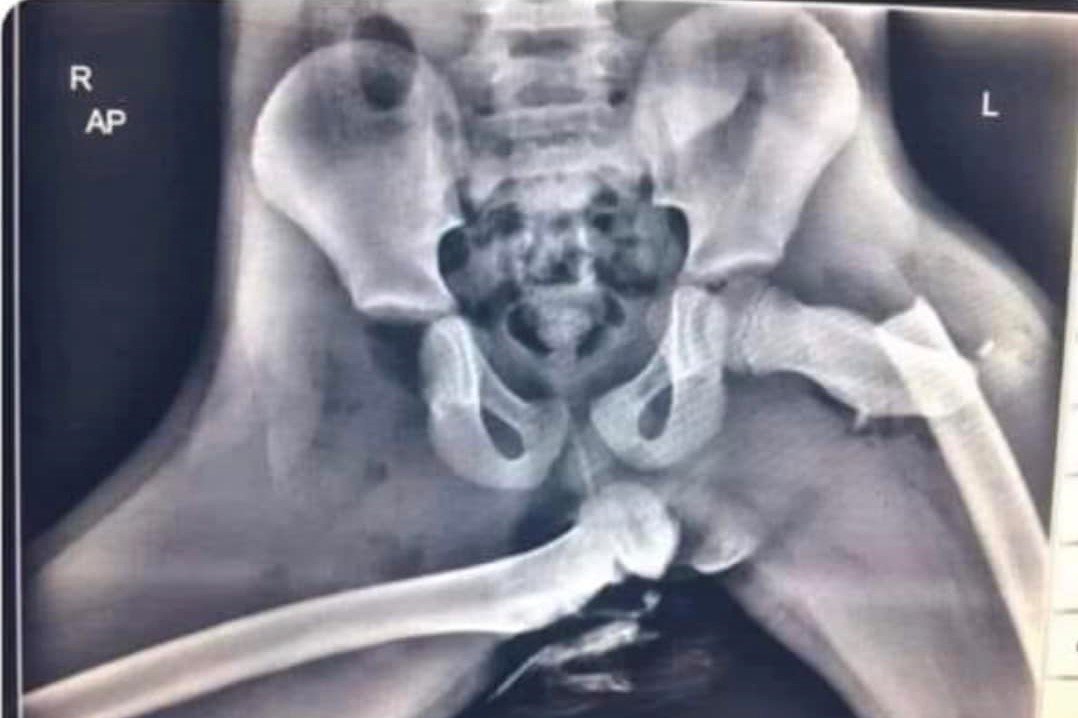

W sieci krąży zdjęcie rentgenowskie strzaskanej miednicy, w wyrwaną ze stawu kością udową. Osoba, która w czasie wypadku samochodowego trzyma nogi na desce rozdzielczej, może nawet stracić życie, a na pewno straci sprawność. Tego chcesz dla swojego dziecka?

Na profilu "Z pamiętnika policjantki" w serwisie Facebook pojawił się wpis, który daje do myślenia. Zdjęcie RTG połamanej miednicy i dosłownie wyrwanej ze stawu biodrowego kości udowej, druga kość złamana.

"To zdjęcie dziecka, które było pasażerem samochodu uczestniczącego w wypadku. Dziecko siedziało na fotelu pasażera. Miało zapięte pasy. Nogi miało położone na desce rozdzielczej. Doszło do zderzenia. Wybuchły poduszki powietrzne. Finał widzimy na zdjęciu. Nigdy nie popełniaj tego błędu. Szerokości na drodze i zawsze bezpiecznie do celu" - pisze policjantka.